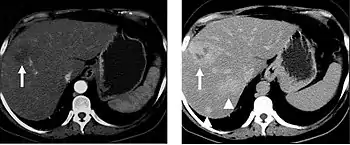

When evaluating hepatic masses, it can be advantageous to have both late arterial and portal venous phase images (biphasic imaging, figure 4) since some tumors enhance briskly during the arterial phase (hepatocellular carcinoma, hepatic adenoma, follicular nodular hyperplasia (FNH), and hypervascular metastasis), but may be occult or difficult to characterize on portal venous phase imaging alone (figure 6). However, it should be stressed that the addition of late arterial phase images is only indicated if one of these tumors is suspected, or if there is a need for further characterization of a hepatic mass, since the large majority of patients will not benefit from the addition of this phase. In addition, if there is a need to definitively characterize a hepatic mass, MRI is generally more sensitive and specific, with no associated radiation dose.

Transient hepatic attenuation differences in the arterial phase may mimic diseases of the liver.